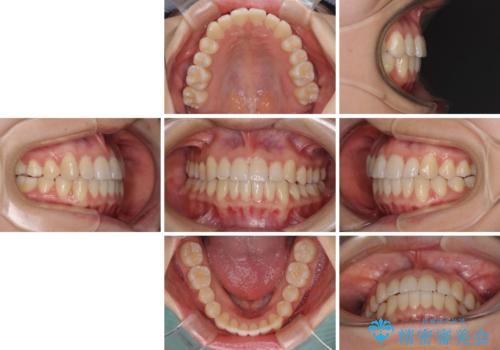

前歯のクロスバイト インビザラインによる矯正治療

- 前歯のクロスバイトを気にして来院された患者様です。

短期間での治療を希望され、ワイヤー装置とインビザラインとで悩んでいましたが、自己管理を徹底すると言うことでインビザラインによる矯正治療を行うこととしました。

しっかりとインビザラインの装着時間を守っていただいたので、1年弱で矯正治療を終えることができました。